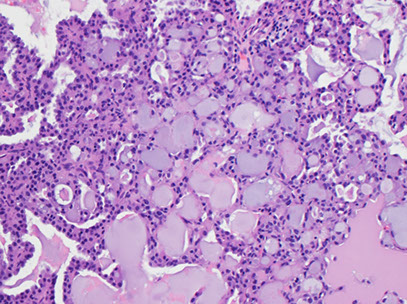

Warthin tumor

- aka Cystadenolymphomatosum or adenolymphoma

Possibly derived from salivary duct remnants trapped in salivary gland LNs; feels doughy

- 2nd MCC salivary gland tumor (up to 1/10 of all)

- 1/10 are multifocal or bilateral

- inc risk in smokers

Micro: oncocytes (abundant granular orange to blue cytoplasm arranged in flat sheets / papillae) scattered and in groups c lymphs and granular debris in background that looks like it contains motor oil

- background nucleated and anucleated squames can be in atypical forms

Tx: resection c preservation of facial n.